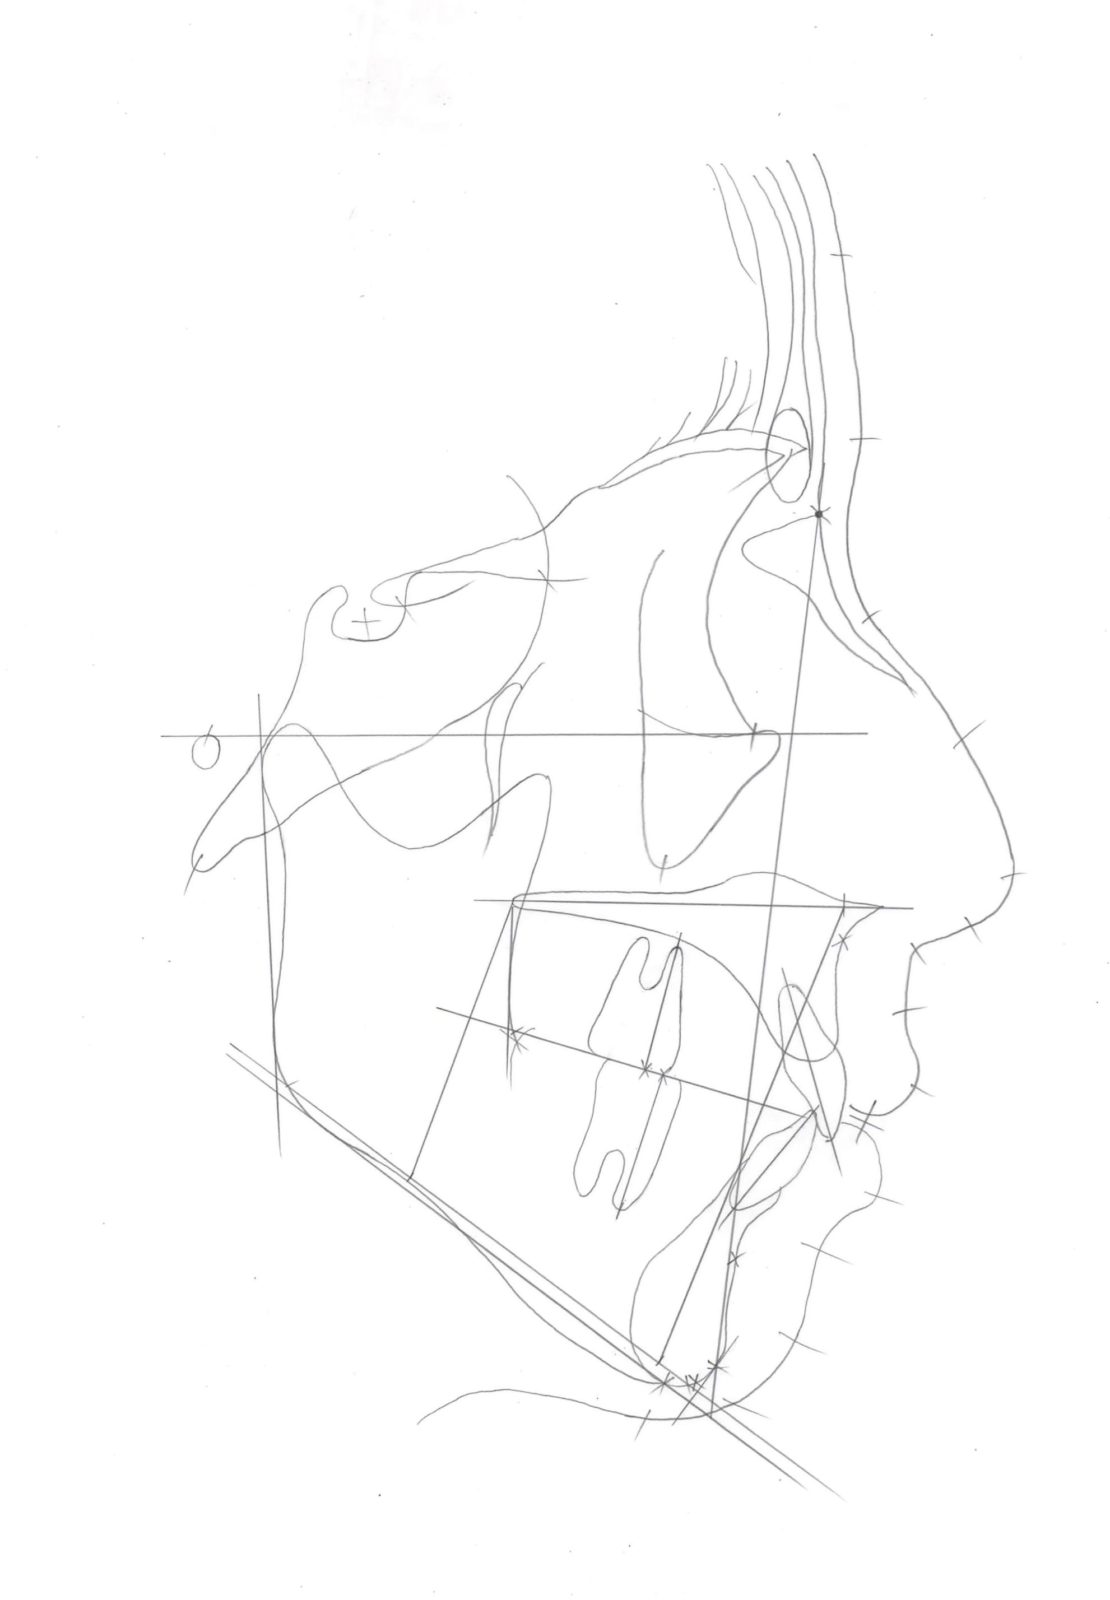

セファロ分析では、まずはじめに骨や軟組織(なんそしき)のトレースを行います。分析に必要な平面や点をプロットしていきます。そして、点の位置や平面同士の角度などを数値化し、標準的な歯並びの良い人の骨格や歯と比べて、上顎骨・下顎骨の骨の位置が前にあるのか後ろにあるのか、上下の前歯の位置が前にあるのか後ろにあるのか、傾斜が大きいのか小さいのかなどを分析します。